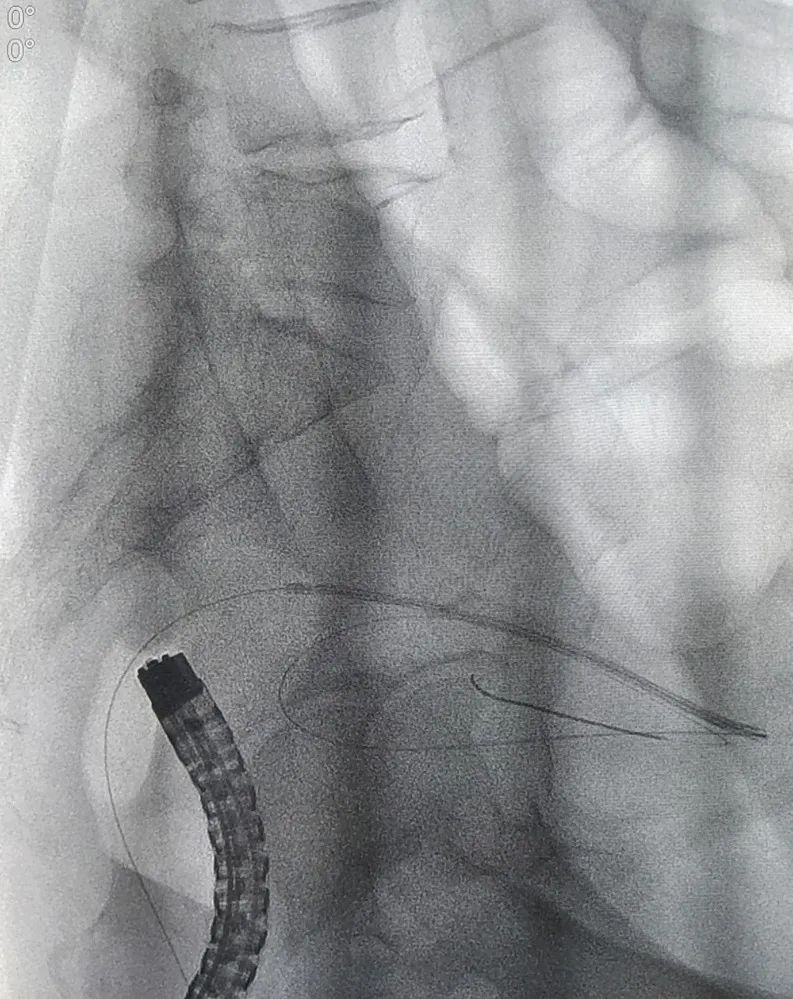

确定诊疗方案后,因患者病情发展较快,消化内科团队为患者开展了急诊肠镜。肠镜检查发现,进镜至距肛缘约 10 cm 处可见一肿物,呈隆起性生长,表面有出血,附有脓苔,考虑直肠恶性肿瘤可能性大,因肠腔水肿、狭窄明显,镜身不能通过,切开刀带导丝进入远端肠道,造影可见肠道呈截断性狭窄。

为快速缓解症状、解除患者疼痛,消化内科郭锐主任及张磊护师结合患者具体情况,决定给予肠道支架置入解除肠道梗阻,使患者免遭肠造瘘的痛苦,为择期手术切除直肠病变做好准备。由于病变导致肠腔严重狭窄,肠道支架置入难度也随之增加,郭锐主任凭借夯实的理论基础及高超的操作技术,通过 DSA 及肠镜联合引导,成功完成了肠道内金属支架置入术。术后患者能自主排便,腹痛、腹胀症状明显缓解,现已出院。

即在肠道狭窄的部位放置一个网状支架将肠道撑开,使狭窄或阻塞部位重新恢复通畅,可作为结直肠癌恶性梗阻的永久或暂时性治疗。肠道支架的过渡性放置,使梗阻性结直肠癌患者的肠道局部和全身状态恢复或接近无梗阻状态,2-3 周后再选择结直肠癌的 I 期手术方式处理,降低造瘘率、改善患者生存质量。肠道支架置入的引导方式有 DSA 引导和肠镜引导,DSA 引导通过注入对比剂能透视到狭窄近段肠腔扩张的程度,以及导丝是否确定在肠腔内;肠镜引导能直接清晰地看到狭窄远段肠腔的情况,尤其是狭窄段外口的具体位置;两者结合对重度狭窄、甚至闭塞的肠腔寻得一丝缝隙,使得支架置入获得成功。